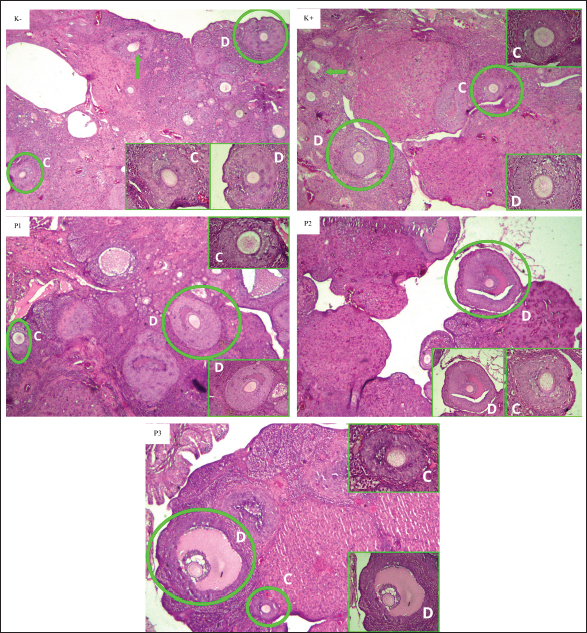

On average, each treatment group was given curcumin nanoparticles with a certain dose before exposure to carbon black 1064 mg/m3, and it was seen that the P1 group had the highest average number of antral follicles, which was 17.67 ± 7.45, while the P3 group had the lowest average number of antral follicles, which was 9.50 ± 5.09, and the P2 group was 16.00.

K(+) was not significantly different (p > 0.05) from the P3 group. This shows that the administration of carbon black in the K(+) group has a real effect on the number of antral follicles and in the P3 group that is exposed to carbon black and the dose of curcumin nanoparticles of 150 mg/kgBB gives similar results to the K(+) group.

The P2 group did not differ significantly (p > 0.05) from the K(+) and P3 groups. In addition, P2 is not significantly different from the (K−) and P1 groups. In the data obtained, it can be seen that P1 does not differ significantly (p > 0.05) from K(−), showing that the dose used in P1 can give an average value that is close to the K(−) value. The mean histopathology of antral follicles can be seen in Figure 3.

Fig. 3. Histopathological description of the antral follicles of the ovaries of white rats (R. norvegicus) given curcumin nanoparticles as a prevention of exposure to carbon black in the K−, K+, P1, P2, and P3 groups with 40× magnification HE staining. The circles and green arrows indicate the antral follicles [tertiary and de graaf follicles (C and D) observed]. In box shows the tertiary follicle (C) and follicle de Graaf (D). The negative (K−) and positive (K+) control groups were given aquades + Na-CMC 0.5% orally, while the treatment group received different doses of curcumin nanoparticles, namely, in the P1 (50 mg/kgBW), P2 (100 mg/kgBW), and P3 (150 mg/kgBW) groups.